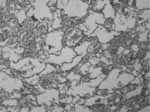

Se encontró hiperplasia del epitelio de la pared bronquiolar en 73 ratones (88%) de los cuales 51 ratones (69.8%) presentaron hiperplasia leve y otros 22 (30.2%) hiperplasia moderada (Foto 1). Los 10 ratones restantes (12%) no presentaron hiperplasia de la pared bronquiolar.

De los 51 con hiperplasia leve, el 33.3% pertenecían al grupo B, el 29.4% al grupo C, y el 37.3% al grupo D. De los 22 con hiperplasia moderada, el 40.9% pertenecían al grupo B, el 22.7% al grupo C yel 36.4% al D.

Todos los animales que conformaron el grupo B presentaron hiperplasia epitelial, de los cuales el 65.4% fue leve, y el restante 34.6% moderada. Del grupo C, el 91 % presentó algún grado de hiperplasia, el 68.2% presentó hiperplasia leve, y el 22.7% moderada.

Todos los animales del grupo D presentaron algún grado de hiperplasia. Estos hallazgos son estadísticamente significativos, con un valor de p < 0,01 (Ver Gráfica 1).